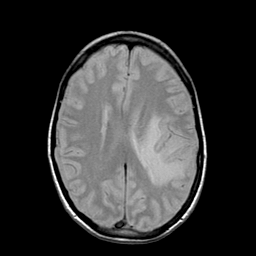

Metastatic bronchogenic carcinoma: proton density-weighted MR -- Slice #14

[Home][Help][Clinical] Slice 14